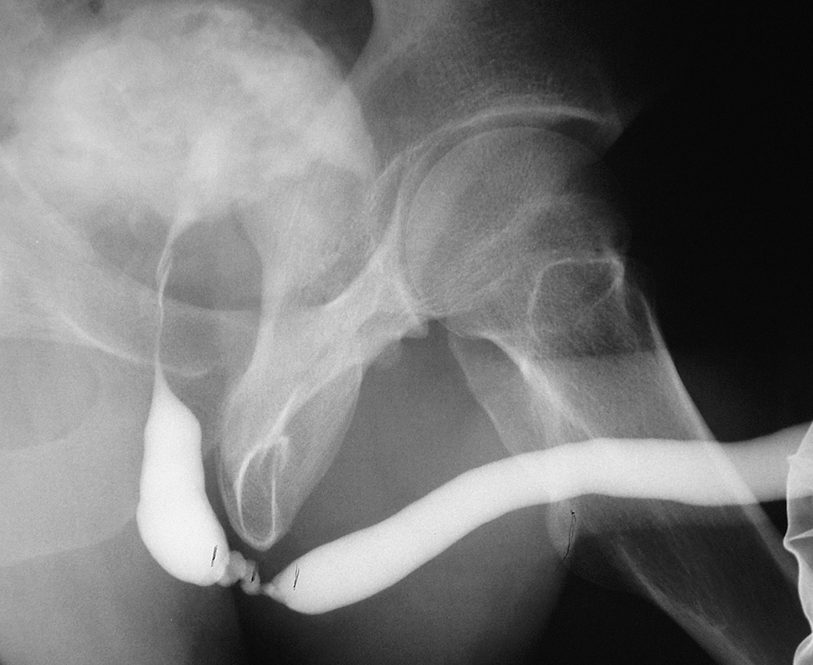

5.3.2 Retrograde Urethrogram and Voiding Cystourethrogram

A longer and more complex bulbar urethral stricture with false passages. Note the concurrent filling of Cowper’s gland